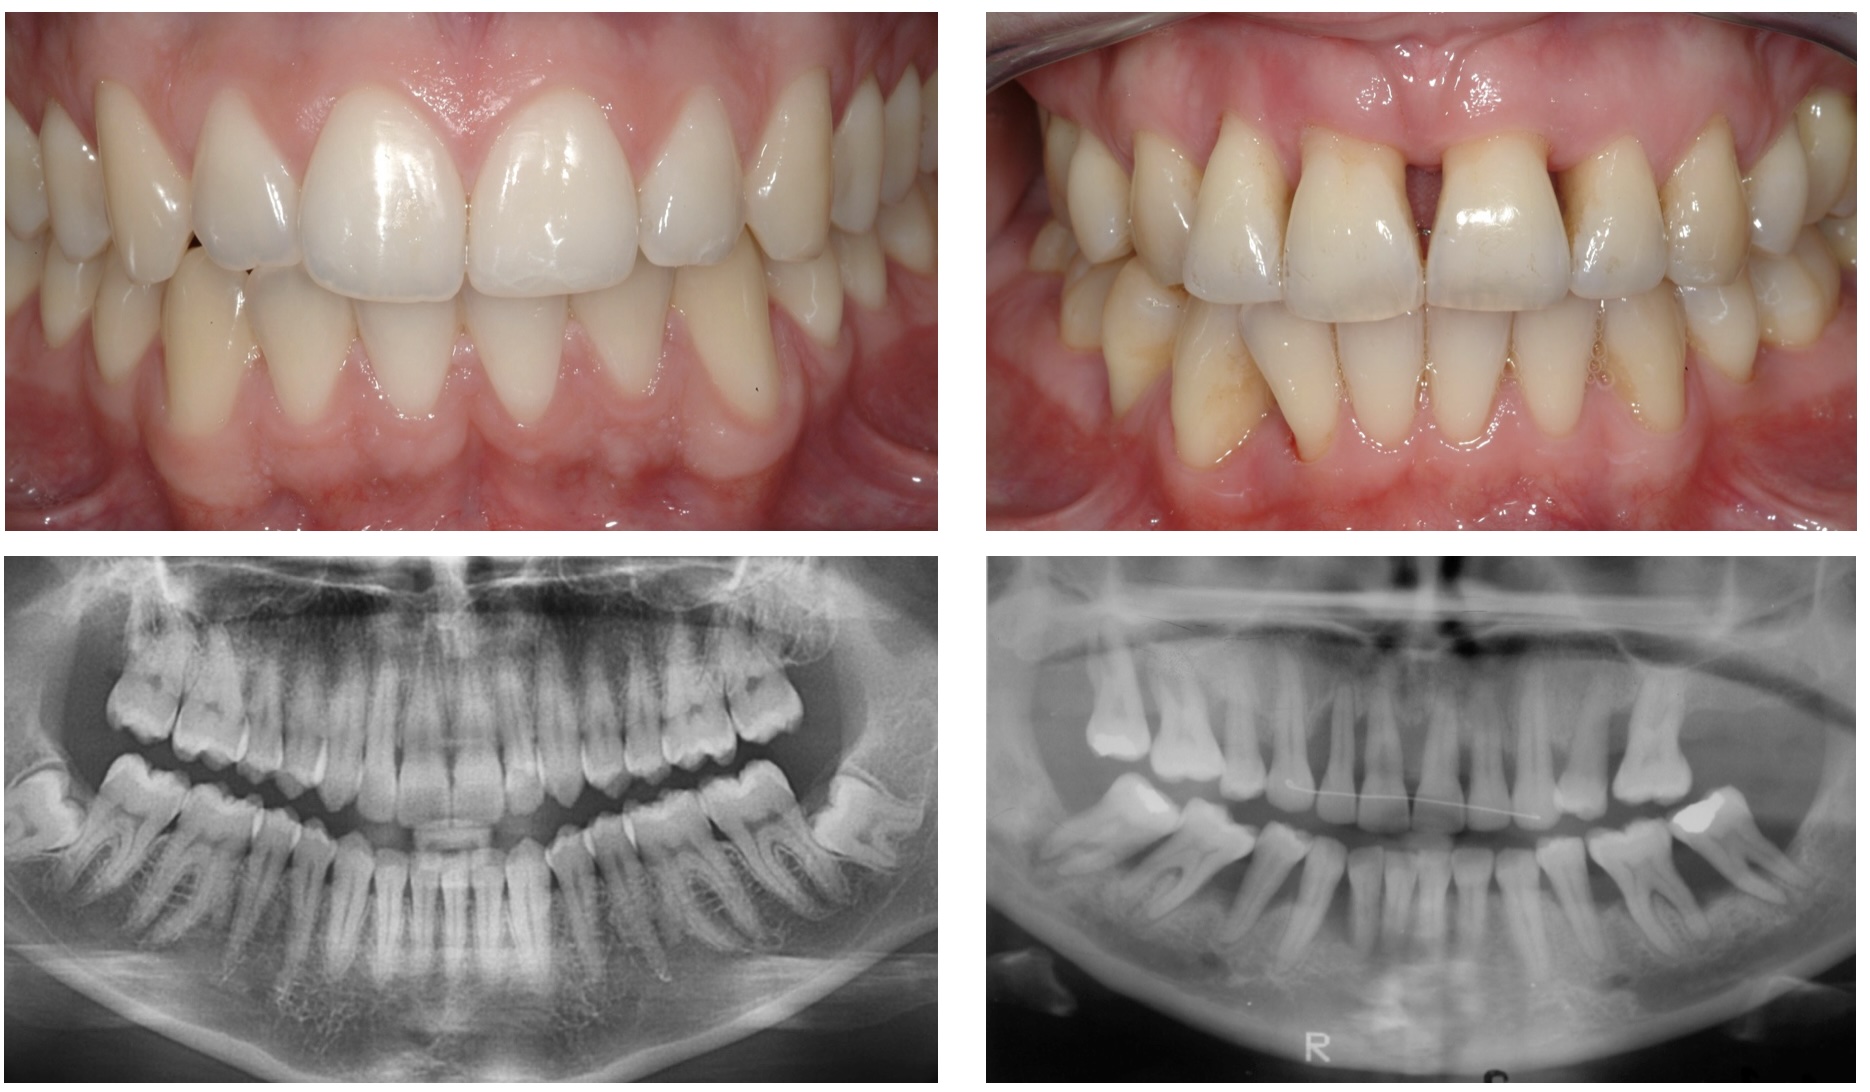

Fasa seterusnya pula adalah tanda-tanda penuaan pada gigi yang akan mula terserlah satu per satu. Terdapat permukaan gigi akan mula merata akibat proses pengunyahan yang menyebabkan kesan retakan halus juga akan mula kelihatan pada permukaan gigi. Manakala di dalam gigi, struktur pulpa gigi yang mengandungi salur darah dan saraf akan mula mengecut. Perubahan-perubahan ini dapat dilihat sama ada melalui pemerhatian secara terus atau melalui filem imbasan x-ray dan seterusnya menjadi petunjuk umur bagi orang dewasa dan orang tua.

Kredit foto-advancedenstistry